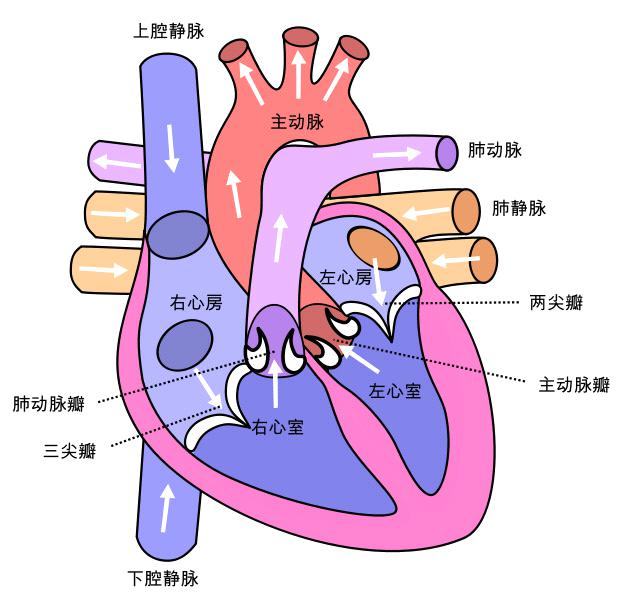

正常的心脏的解剖结构如下图:

可以看到心脏有以下4个心腔(chamber),位于心脏上方的心房(ateria)较小,位于心脏下方的心室(ventricle)较大。

右心房(right atrium):右心房接收来自人体的低氧血液。 -

右心室(right ventricle):右心室将低氧血液泵送至肺部,使肺部充满氧气。 -

左心房(left atrium):左心房从肺部接收富含氧气的血液。 -

左心室(left ventricle):左心室将富含氧气的血液泵送至全身。

为了让血液流入或流出 4 个心腔,

心脏有 4 个瓣膜:

三尖瓣(tricuspid valve):三尖瓣允许缺氧的血液从右心房流向右心室。 -

肺动脉瓣(pulmonary valve):肺动脉瓣将血液从右心室泵入肺部,使血液获得氧气。 -

二尖瓣(mitral valve):二尖瓣使富含氧气的血液从左心房流向左心室。 -

主动脉瓣(mitral valve):主动脉瓣将富含氧气的血液从左心室泵向全身。